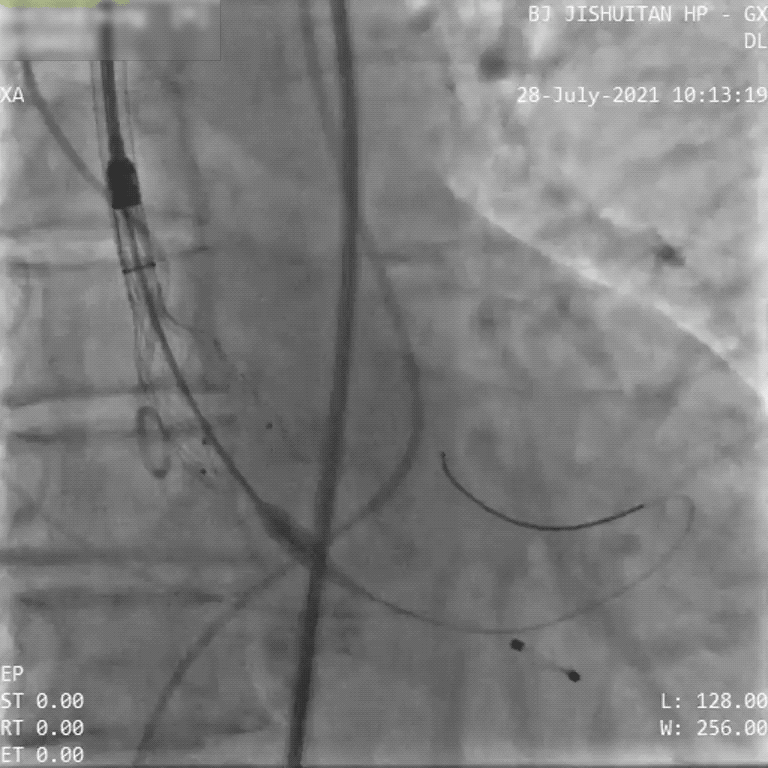

完成PCI手术后,术者团队行主动脉根部造影,确认瓣环结构、瓣叶活动等情况符合术前评估结果,选择经右侧股动脉入路,予以20 mm球囊进行扩张后,植入VenusA-Plus® L23型号瓣膜。

首次释放后发现植入位置不理想,利用VenusA-Plus®的可回收功能对瓣膜进行回收,重新精准定位后再次释放瓣膜。造影提示冠脉无阻塞,轻微主动脉瓣反流,无瓣周漏,术后即刻超声提示最大流速不足200cm/s,最大压差16mmHg,血压恢复至105/56 mmHg。术后患者状态恢复良好,已平稳出院。